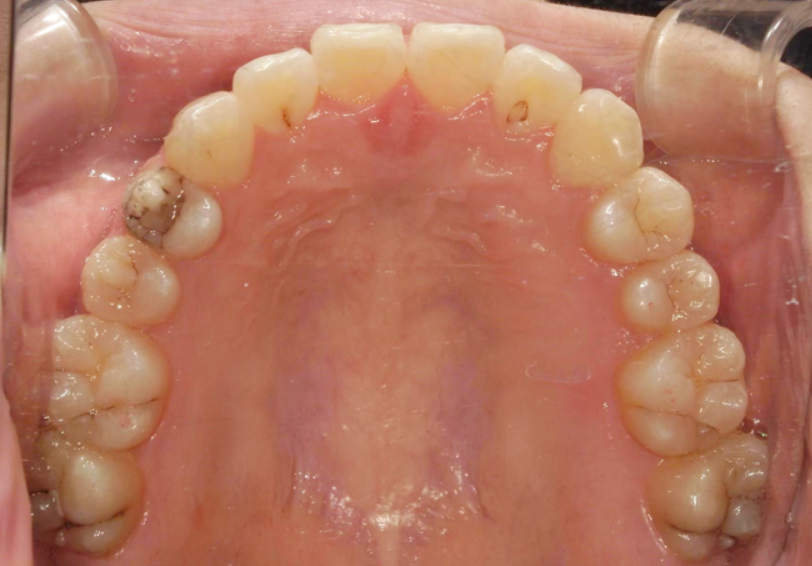

BEFORE